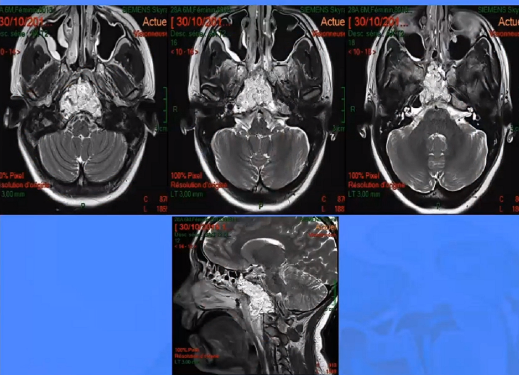

▼这是几年前做的一个手术,先把鼻中隔先推开,然后推开那些正常的组织,这里磨掉枕髁,暴露舌下神经管。虽然很具有挑战性,但是手术做得还是不错的,我们对病人进行了长期的随访,因为我们把全部的就是切开的软组织都复位了,所以看起来还可以,经过内固定以后,病人的颅颈交界区是很稳定的。

▼这是术后的MRI,大家看到的高信号的是脂肪组织,我觉得利用内镜到达颅颈交界区更简单。

▼这个病例,它影响了颈1颈2,然后没有侵袭到硬膜内,我就不考虑用内镜了。考虑到脑脊液的释放等问题,这里我用了后外侧的一个入路。利用45度的内镜往上看,往上磨除岩骨的后方,可以一直暴露颈内动脉的岩骨段,然后海绵窦段。然后在显微镜下我们可以进行双手的操作,神经外科医生就比较熟悉的了。我们在做手术切除肿瘤切完了之后,还要进行固定。

▼这是术后的MRI